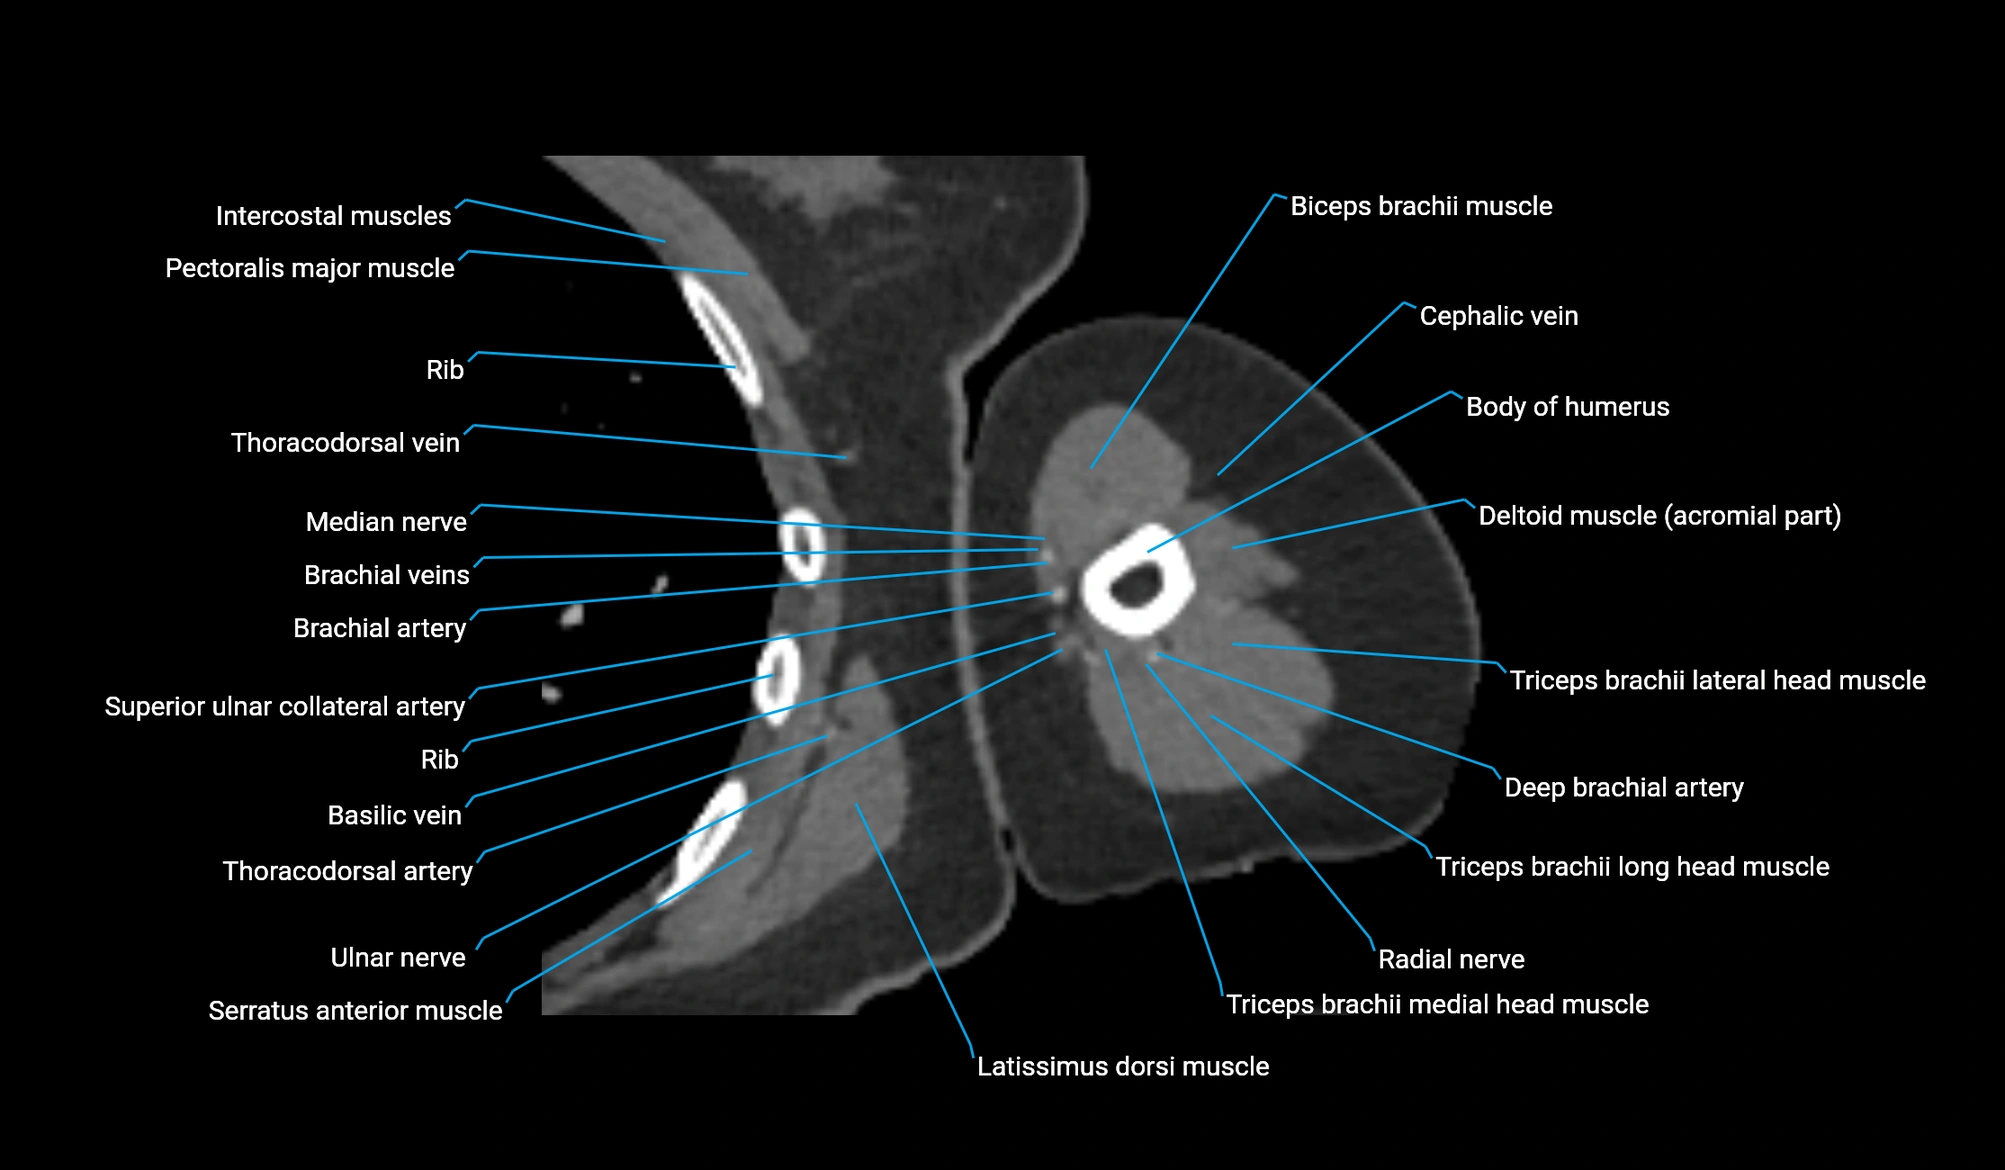

- Body of humerus

- Brachial artery

- Cephalic vein

- Deep brachial artery

- Median nerve

- Radial nerve

- Superior ulnar collateral artery

- Teres major muscle

- Thoracodorsal artery

- Triceps brachii muscle

- Ulnar nerve